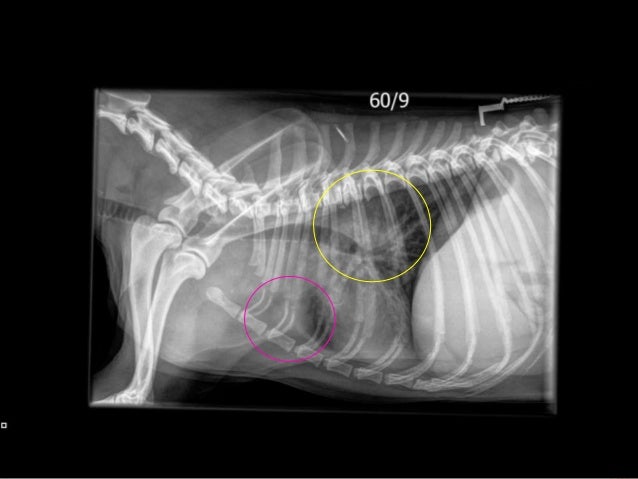

Lymphoma In Dogs

dogs lymphoma lymphadenopathy ultrasound splenomegaly